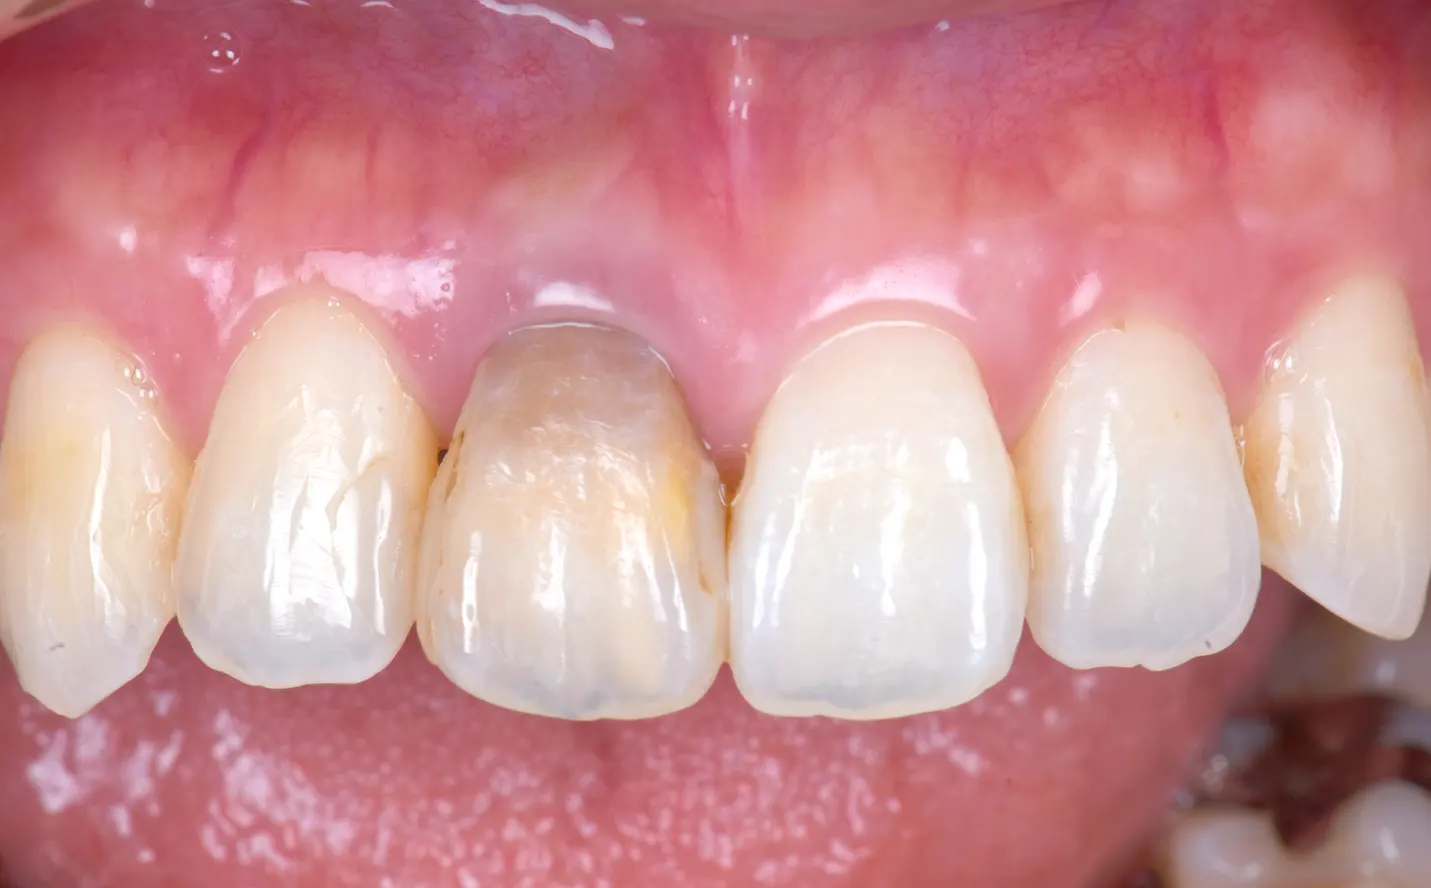

審美治療症例

【症例1】

主訴

黒くなってしまった前歯を治したい

年齢・性別

30代女性

治療内容

右上1に対して

・ウォーキングブリーチ

・ファイバーポスト

・プロビジョナル

・ジルコニアクラウン

期間

3ヶ月

費用

181,500円